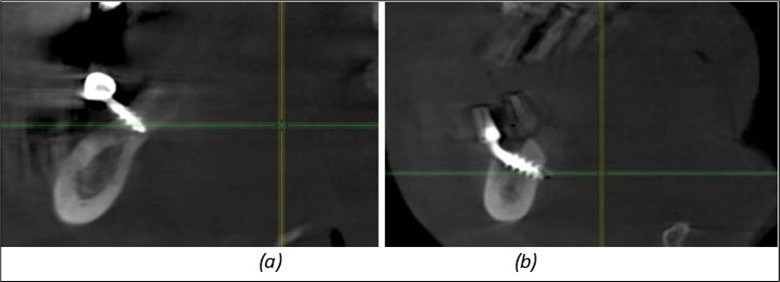

Figure 9.Implants in the pterygoid plateau area: (a) TPG implant fixed in the maxillary-sphenoid junction area, quadrant 1; (b) TPG implant fixed in the maxillary-sphenoid junction area, quadrant 2.

Figure 10.Implants in the palatal sinus cortical area to avoid bone grafting: (a) BCS implant partially fixed in the graft material mass, partially in the palatal cortex; (b) Implant fixed in the palatal cortex at the junction with the nasal cortex, behind the graft material mass.